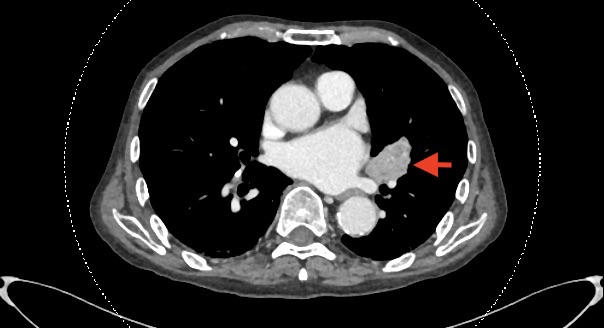

偶然发现左肺门占位:中央型肺癌?

腹主动脉瘤破裂,后腹膜血肿。管腔呈新月型是特征性表现。瘤体最大直径约9cm。